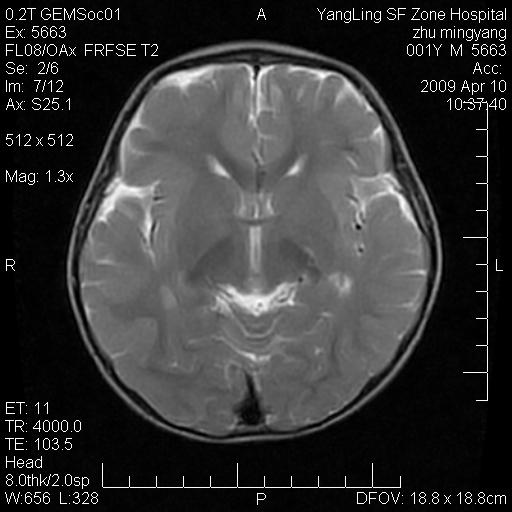

患者:1岁半,两天前外伤收住我院,ct检查小脑占位

考虑星形细胞瘤,建议增强

髓母细胞瘤或血管母细胞瘤,增强后可以鉴别;影像资料见 <。鱼博浪老师的《中枢神经系统ct与mr鉴别诊断》 小脑部肿瘤章节。

髓母细胞瘤或血管母细胞瘤!支持!

支持考虑髓母细胞瘤

考虑----髓母细胞瘤可能性大

考虑髓母细胞瘤或室管膜瘤。

支持髓母细胞瘤。

考虑髓母细胞瘤。

考虑髓母细胞瘤或星形细胞瘤

考虑髓母细胞瘤.

考虑髓母细胞瘤可能性大。

小脑肿瘤.考虑髓母细胞瘤可能.

就病灶部位及临床资料首先考虑髓母.